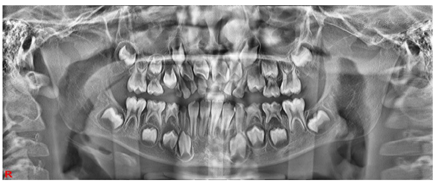

X线影像显示:85根管内阻射影像,达根尖,近中根管根尖有根充物溢出影像,根尖周未见透射影像。84根管内阻射影像,达根尖,远中根尖周有透射影像,波及44恒牙胚硬骨板,近中根尖有根充物溢出影像。83根管内阻射影像,致密,根尖有糊剂溢出,根尖周未见透射影像。73M、D、74MOD、75DO龋洞,发黑,探诊质硬,冷诊未诉不适,叩痛(-),根尖区黏膜无异常(图3)。

X线影像显示:73M、D透射影像,达牙本质中层,根尖周未见异常。74MOD透射影像,近髓腔,根分叉处可见透射影像,34恒牙胚硬骨板完整,根尖周未见异常。75DO透射影像,近髓腔,根分叉处可见透射影像。远中根尖周可见透射影像,波及35恒牙胚硬骨板。55O、P、65O、P龋坏,探诊质硬,冷诊正常,叩痛(-)。14、24萌出,松动I度,牙合面近远中向牙龈覆盖(图4)。

X线影像显示:14、24未见牙根影像。53D龋洞,发黑,探诊硬,冷诊正常,叩痛(-),根尖区黏膜无异常(图5)。X线影像显示:53D透射影像,达牙本质中层,根尖周未见异常。52、62松动II度,腭面近中呈黄褐色,探诊质硬。51、61拔牙创区牙龈无红肿,牙龈黏膜未完全愈合。16、26、36、46牙面窝沟白色样封闭物,封闭物完好(图6)。